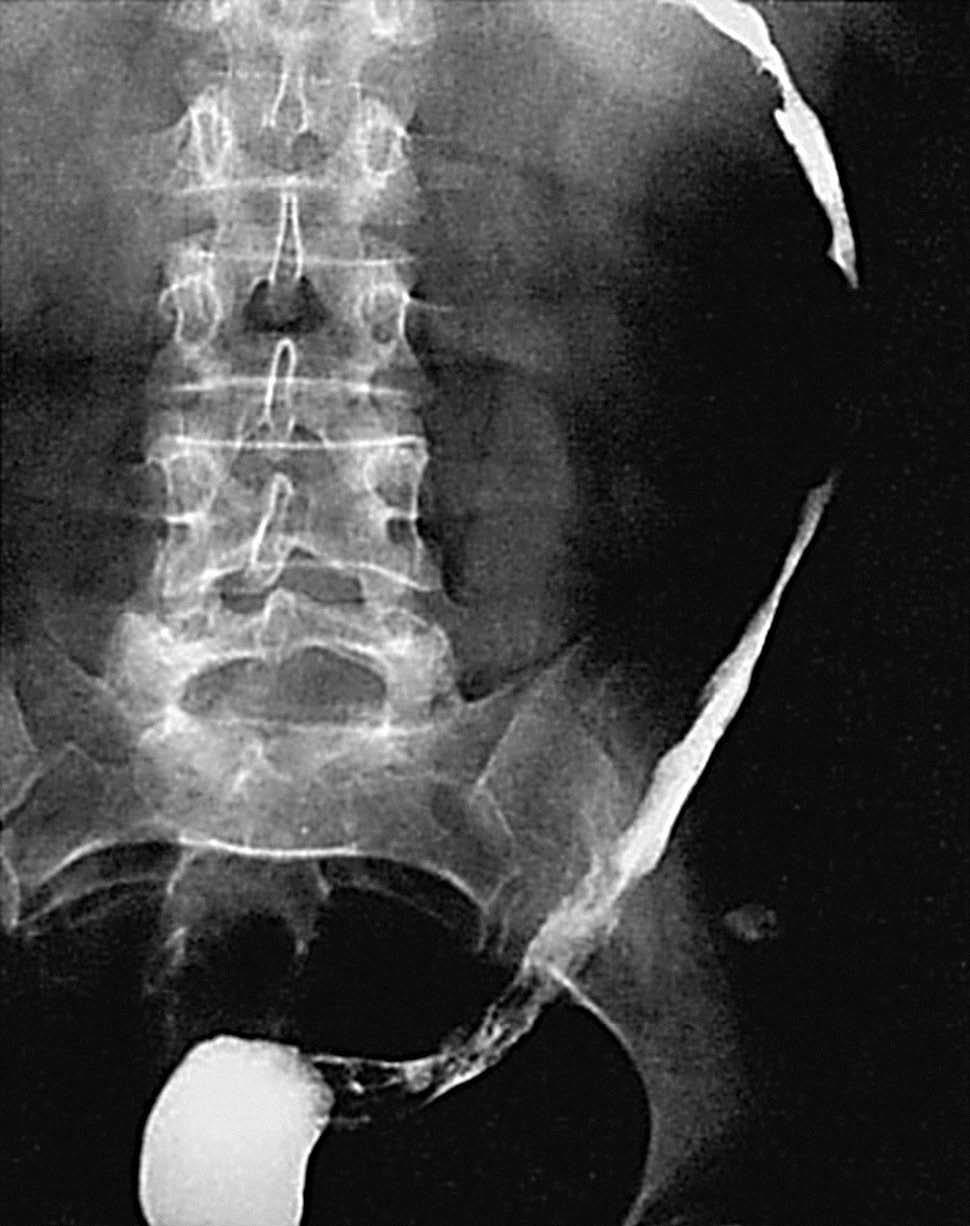

La EC se define como un proceso transmural inflamatorio crónico de etiología desconocida. De carácter recurrente, segmentario y granulomatoso, tiende a provocar complicaciones tales como abscesos y trayectos fistulosos. Se localiza en cualquier segmento del tracto digestivo, desde la boca al ano, aunque asienta de forma preferente en el íleon terminal, en íleon proximal y colon ascendente (fig. 1). Se acepta que en un 55% de los casos hay afectación del íleon terminal y del colon, en un 30% de los casos sólo de intestino delgado y que la afectación exclusiva del colon acaece en un 15%9.

Fig. 1.--Enfermedad de Crohn, afectación segmentaria del tracto digestivo con localización duodenal (A) e ileal (B) en el mismo paciente.